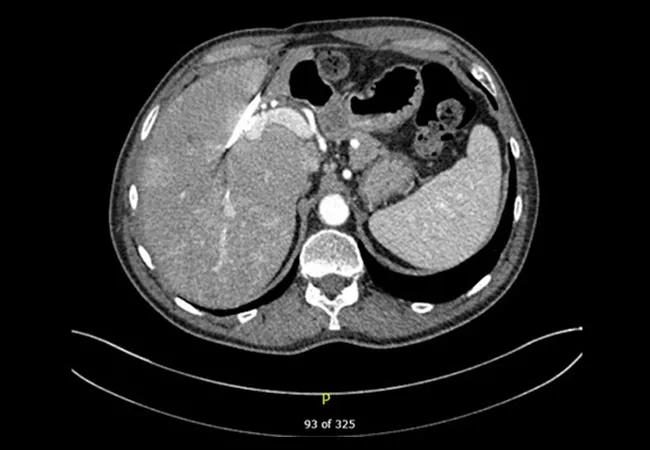

In April 2016, he presented to Cleveland Clinic where he was studied with both with an MRI and a CT scan (see main image above) that showed an atrophic left hepatic lobe, a right-sided internal-external percutaneous transhepatic biliary drainage catheter with mild segmental intrahepatic biliary dilatation in the right lobe, as well as a markedly atrophic left lobe. The left hepatic duct was completely obstructed and undrained.

CT scan showing the liver after left hepatectomy with a new hepaticojejunostomy.